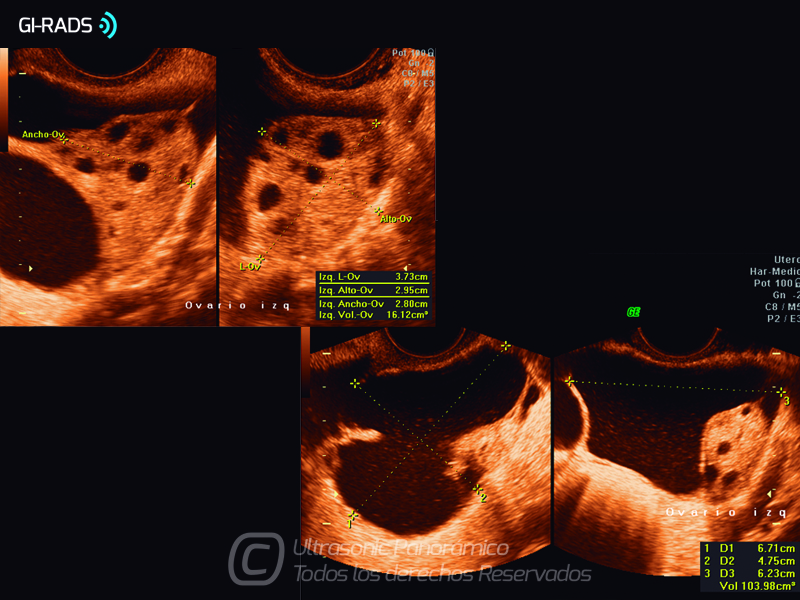

Patologías Benignas – Pseudoquiste de Inclusión Peritoneal

• Patologías Benignas – Pseudoquiste de Inclusión Peritoneal